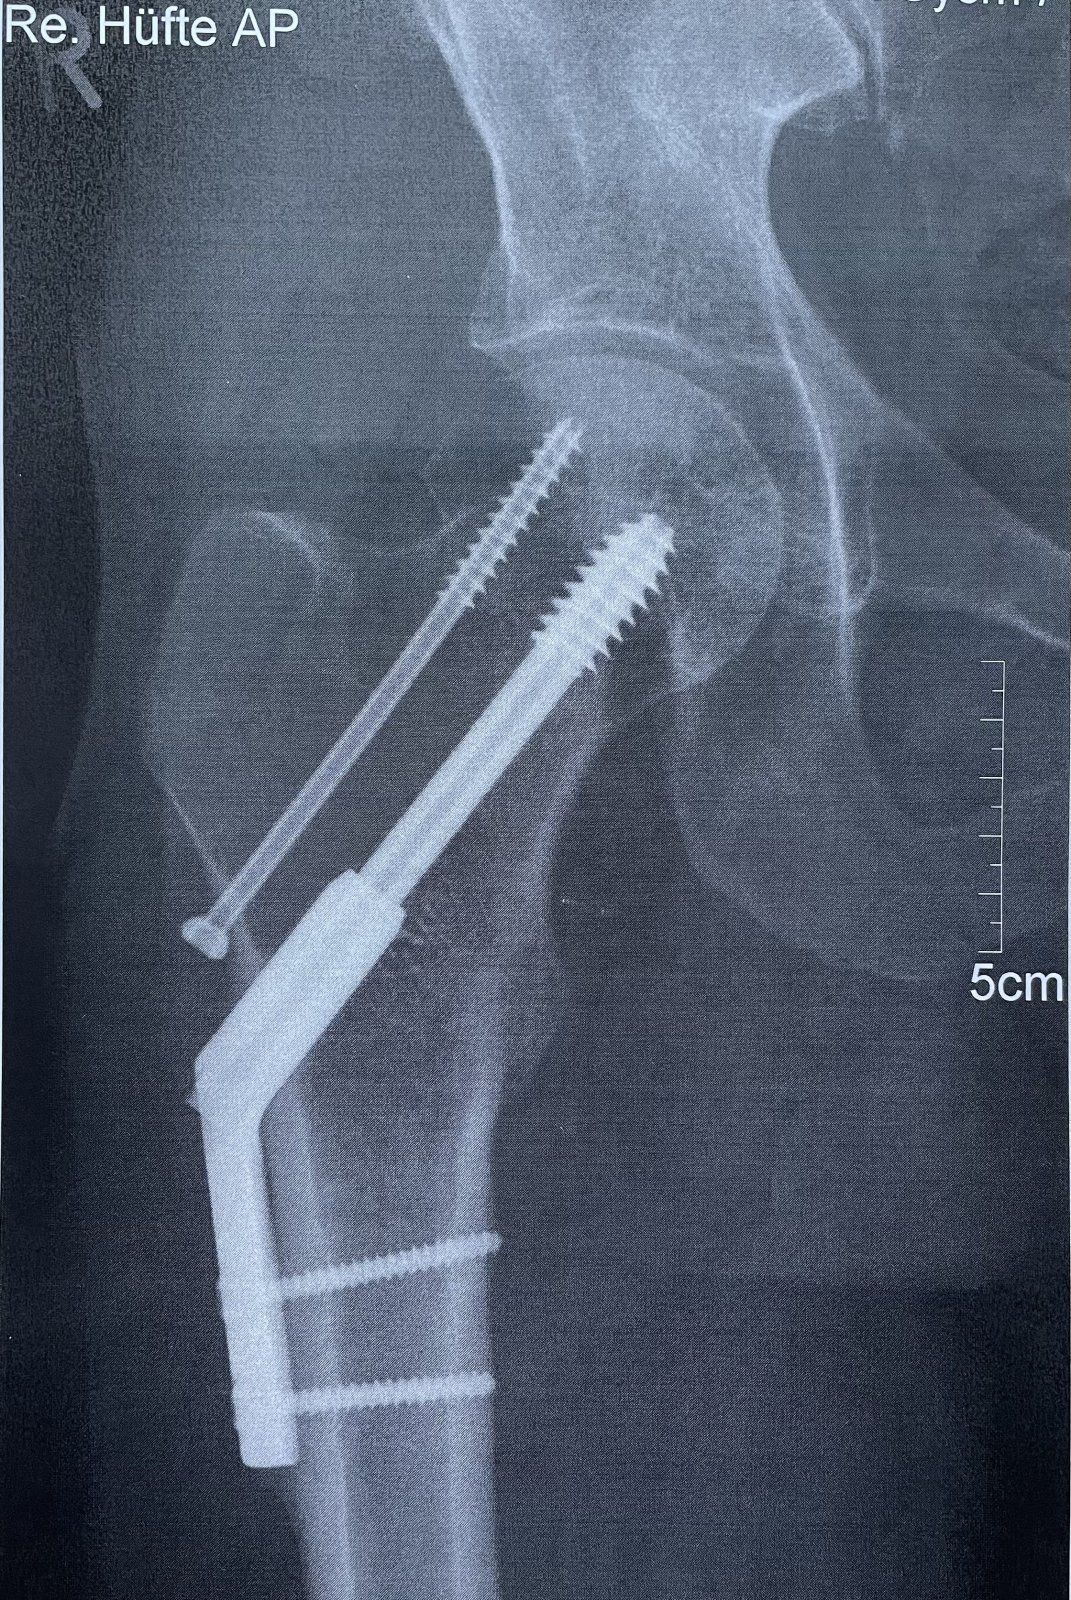

Mir geht es soweit ganz gut, Fäden wurden letzte Woche gezogen. Ist auch gut verheilt, nur eine kleine Stelle noch nicht. Ich creme fleißig mit Narbensalbe. Am Freitag wird geröntgt. Ich habe meine Schrauben trotz mehrmaliger Nachfrage leider nicht bekommen. Bin mir nicht ganz sicher, aber ich glaube, eine ist bei der Entfernung zerbrochen. Hatte ja eine Spinalanästhesie....